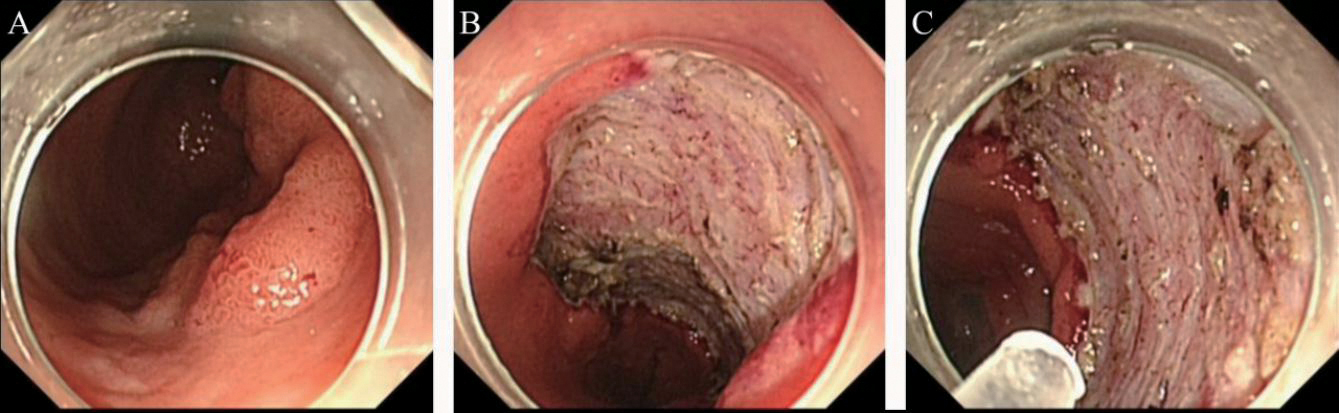

2.针对胃镜下ESD术后止血的应用

患者男,53岁,胃窦小弯Ⅱa+Ⅱb病变,术中使用复合微孔多聚糖止血粉预防出血,术后观察2 d后出院,无术中及迟发性出血发生,见图2

图2 胃镜下ESD术后止血

A:行ESD术胃黏膜Ⅱa+Ⅱb病变;B:创面以复合微孔多聚糖止血粉喷洒止血